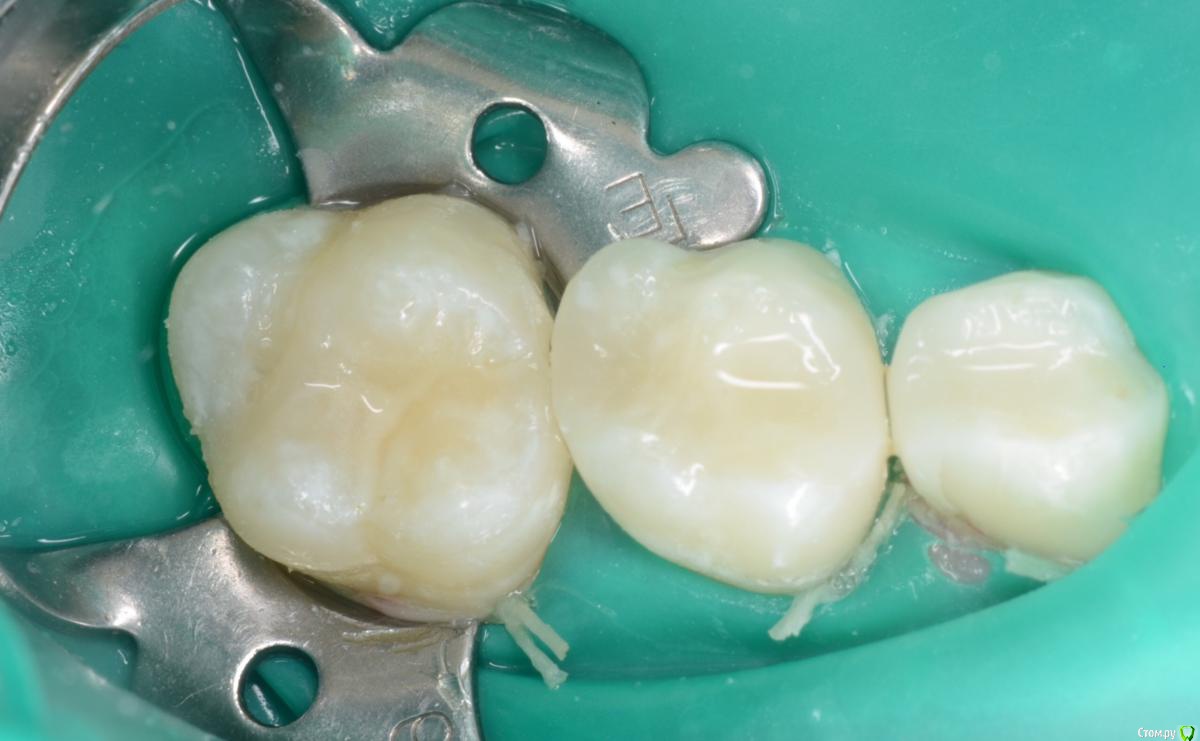

CRAZYDUCK Опубликовано 19 мая, 2018 Автор Поделиться Опубликовано 19 мая, 2018 Лечение кариеса 8.4 и 8.5 , герметизация 4.6 . 3 Ссылка на комментарий

CRAZYDUCK Опубликовано 19 мая, 2018 Автор Поделиться Опубликовано 19 мая, 2018 (изменено) Костя , 7 лет .Лечение кариеса 1.6; обратимый пульпит 5.4 и 5.5 .5.4 заполирован по контакту после снятия коффера, платок два раза меняла ( порвала по каоьакту). Фото после снятия коффердама уже не было сил сделать ;( ( новая ассистент, еще не сработались - дольше все делаем , чем с другим ассистентом .Ещё прийдет на лечение - сделаю . Изменено 19 мая, 2018 пользователем CRAZYDUCK 3 Ссылка на комментарий